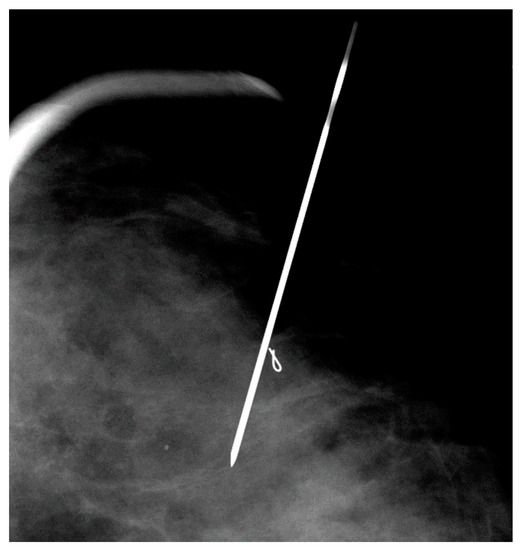

Figure 6. Mammographically-guided SLNB with two spinal needles.

Two tuberculin syringes are added to the standard procedure tray (Figure 4) for mammographically-guided SLNB. The radiopharmaceutical is kept in a lead container until the time of injection. Four mL of Tc-99m-sulfur colloid is injected in divided doses through the localizing needles (Figure 5). Hawkins, Homer, spinal (Figure 6) and Kopans needles have been used for mammographically–guided SLNB. After the injection of Tc-99m-sulfur colloid, saline is injected through tuberculin syringes to flush the localization needles (Figure 7).

Mammographically-guided SLNB has been performed on known cancers, suspicious masses and groups of calcifications, excisional biopsy cavities and metal clip markers (Figure 8) placed under stereotactic and sonographic guidance. While mammographically guided SLNB is often performed with two or more and needles, ultrasound-guided SLNB is usually performed with one needle (Figure 9 and Figure 10).